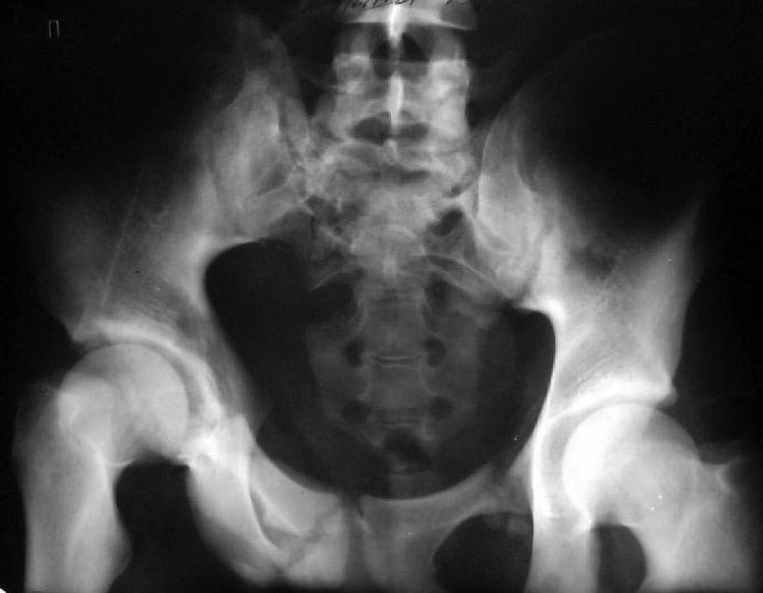

Для информации к размышлению о возможности исправления имеющейся деформации предлагаю похожий случай.